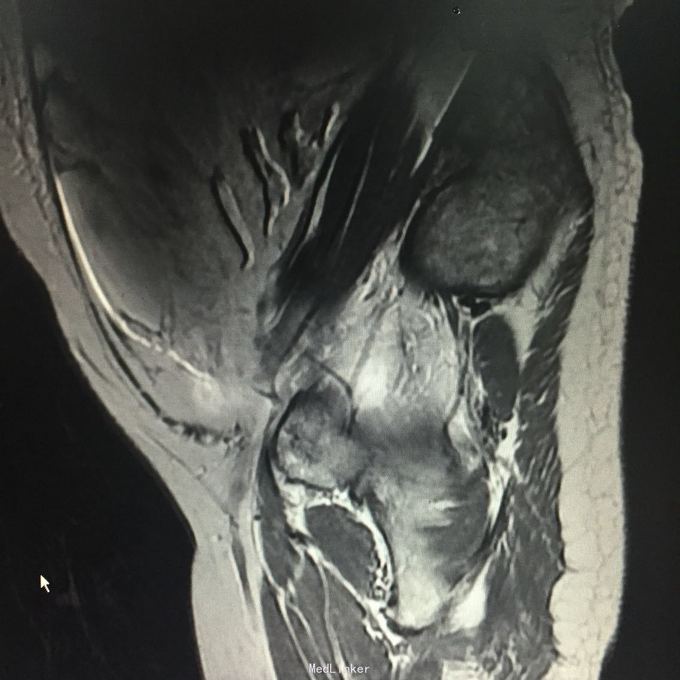

查体:腹围93cm,腹部膨隆,腹肌紧张,全腹部可扪及实性占位,移动性浊音可疑阳性。入院查CA125 472U/ml,HE4 609pmol/l,行B超引导下腹腔穿刺,抽出腹水1000ml,腹水病理:癌细胞。行全腹MR:道格拉斯窝占位性病变,考虑为恶性肿瘤(左侧附件来源),并大网膜、肠系膜、腹膜广泛转移,腹腔大量积液,肝S7/8段包膜下异常灌注灶。

入院诊断:盆腹腔肿物。行剖腹探查术,术中见,腹腔积血500ml,全腹及盆腔簇集状分布大量烂肉样赘生物,腹膜厚,表面密集分布肿瘤组织,子宫及双附件封闭,未探及,考虑手术出血风险大,与患者家属沟通后,暂予以行姑息治疗,遂予以行腹式盆腹腔肿物部分切除术,术中出血1000ml。术后病理:符合癌肉瘤,结合临床发病部位,考虑为卵巢恶性苗勒氏管混合瘤。术后诊断:卵巢恶性苗勒氏管混合瘤IV期。